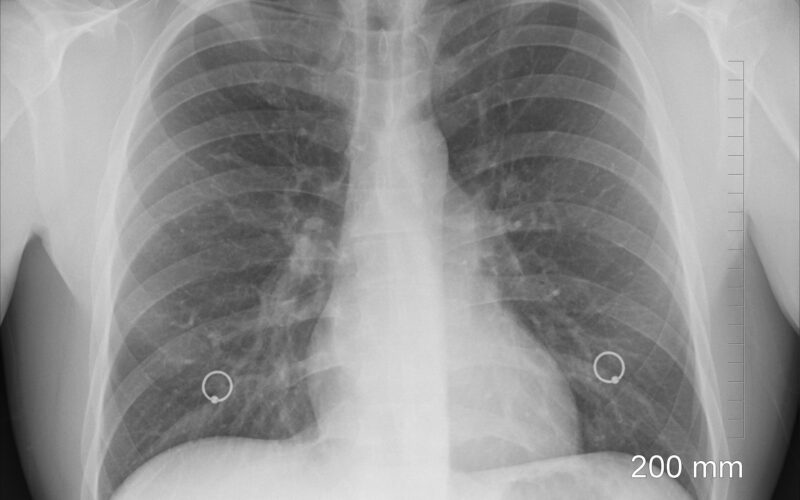

Dr. Jakopović: Post covid može izazvati fibrozu pluća što nekad završava transplantacijom

- Kako je došlo ljeto i cijepljenje, imamo manje post covid bolesnika. Ima ljudi koji stvarno jako dugo zadržavaju teške plućne bolesti - nedostatak zraka pri najmanjem naporu, stalni kašalj. Najčešće to ide prema fibrozi pluća, st…